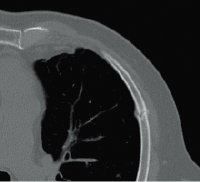

Клинические изображения

Для снижения лучевой нагрузки и повышения качества визуализации в КТ SUPRIA используются алгоритм интеллектуального перераспределения дозы IntelliEC и современный метод итерации IntelliIP, позволяющие провести сканирование с очень низкими значениями доз и получить изображения необходимого диагностического качества. В результате лучевая нагрузка на исследуемую область существенно снижается при сохранении высокого качества визуализации, особенно на уровне плотных паренхиматозных органов.